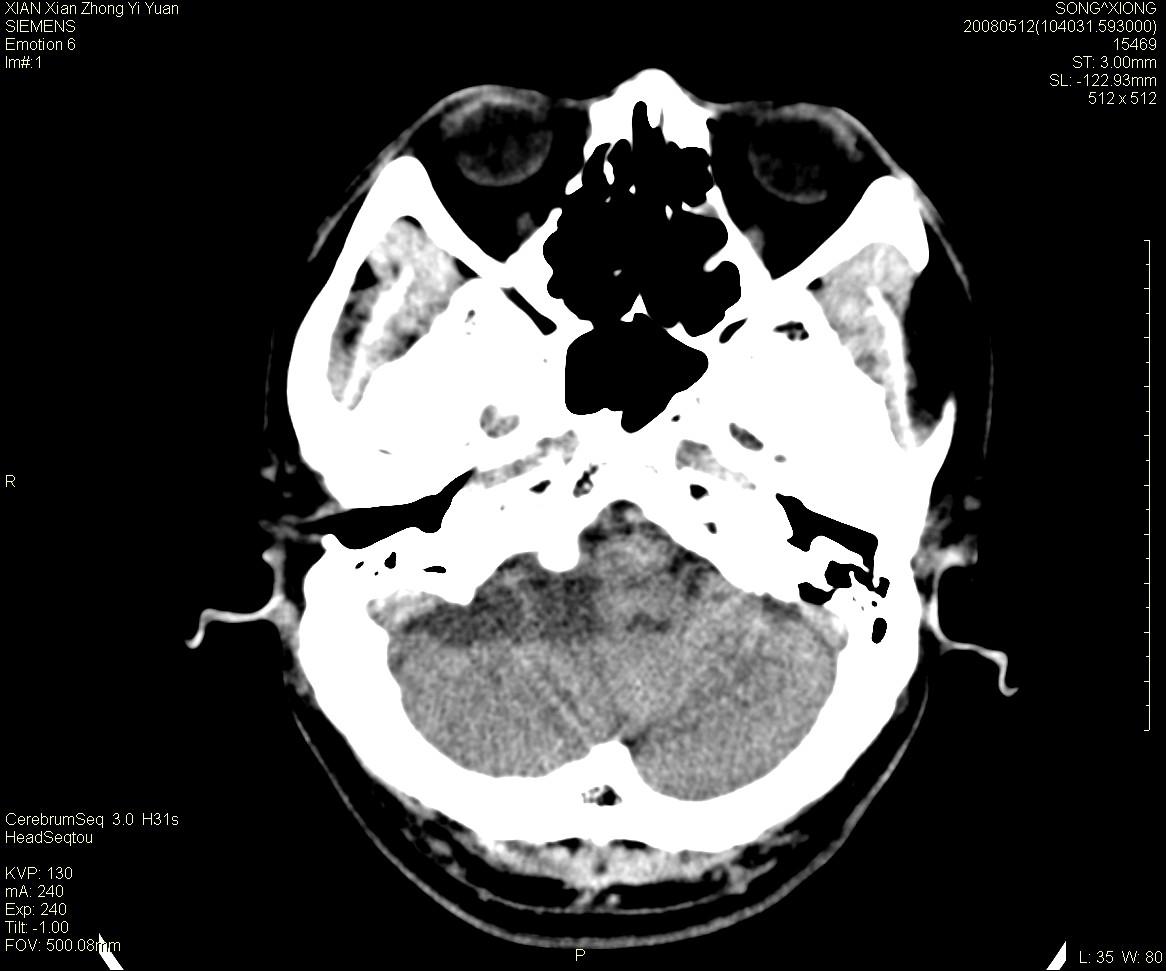

右侧内耳道慢性增宽,内耳道口出可见稍高密度影,桥小脑角池可见以较大低密度影,内缘较清,小脑、脑干、第四脑室受压、移位。

考虑:听神经瘤。

骨窗显示内听道扩大,考虑右侧听神经瘤

典型的右侧听神经瘤。